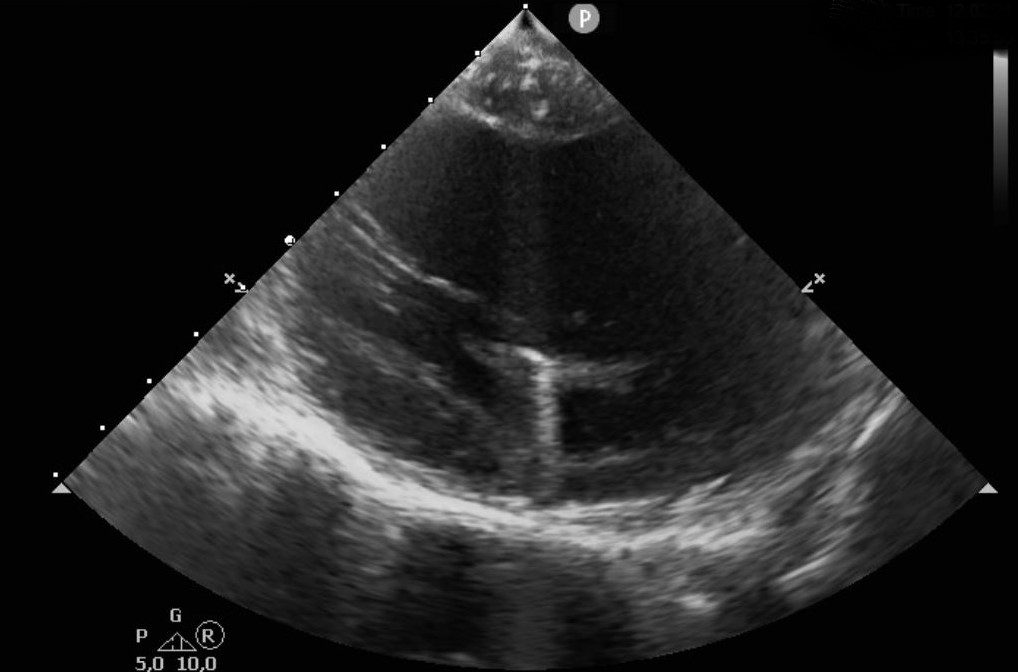

#ICEeyes and #HDmapping for ablation of papillary muscle VAs. Anatomical and electrophysiological information for a successful treatment. Case 1 (intial experience with NavX PM-mapping)

thegellergroup's tweet image. #ICEeyes and #HDmapping for ablation of papillary muscle VAs. Anatomical and electrophysiological information for a successful treatment.

Case 1 (intial experience with NavX PM-mapping)